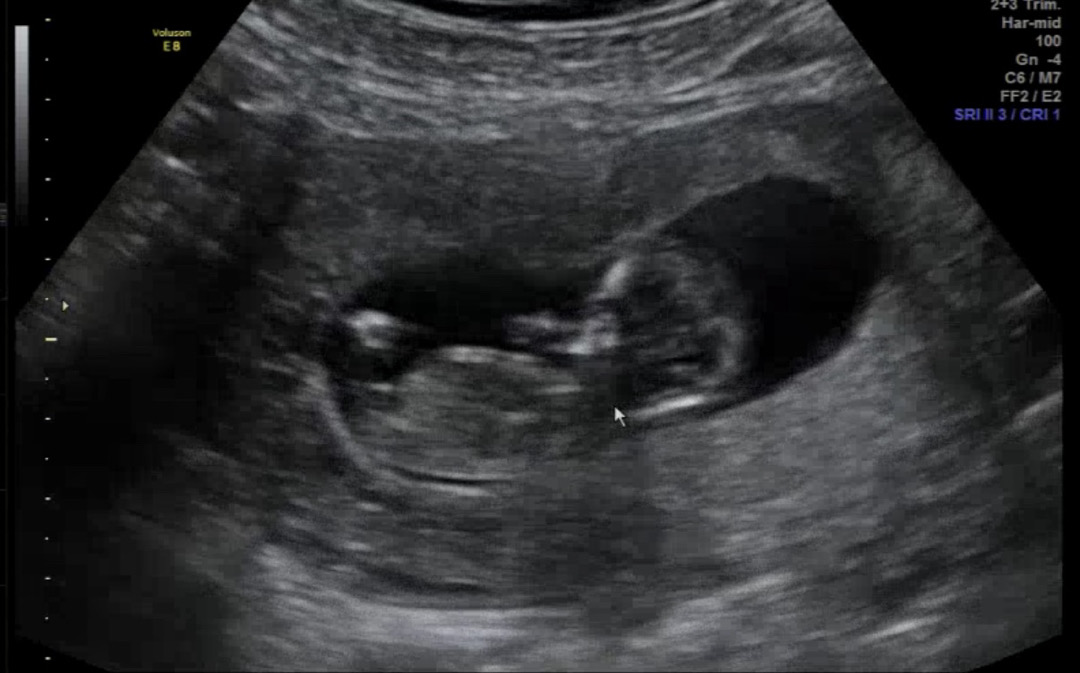

11주 2일 초음파, 아기는 11주 6일 크기였어요. 각도법 사이트, 댓글, 지피티도 모두 딸이라고 했는데!!!💕 니프티 결과는 🩵아들🩵이랍니다! (현재 12주 5일) 대문자 T 테토녀 저는 아들맘을 꿈꿨는데 아들맘이 되었어요! 딸을 원하시는 분들, 아들 원하시는 분들! 우리 모두 그저 건강하고 예쁜 아기 순산하길 바래보아요🫶🏻

축하드려요~ 촘파에 손가락빨고잇는거 같이보이는데 넘나귀엽네요! 🥹 저도 다음달에 니프티랑 1차 기형아검사 하러가는데 아가 성별 너무 궁금해요ㅠㅠㅎㅎㅎ